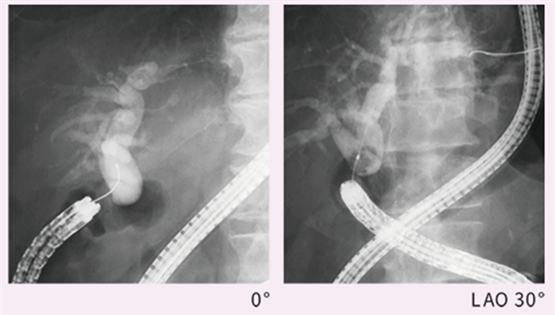

肝门部胆管癌,正面观察可见左右分叉部(a),在将C臂向左旋转20°后病变变得不可见(b),向右旋转10°后病变部位清晰可见(c)

胆道重建后胆肠吻合口狭窄,继发肝内胆管结石。垂直投照时(左),左右肝管汇合处影像重叠,无法观察。调整C臂角度后(右),避免重叠,观察更清楚。